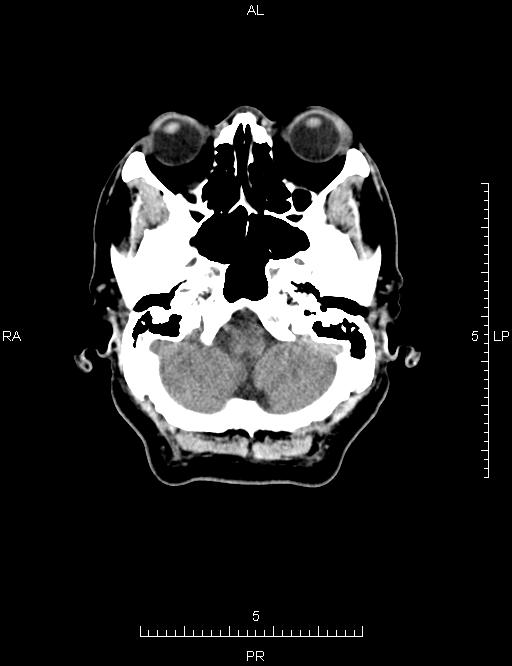

CT50102:头颅CT

男,54岁,头痛、头晕3天。

右侧额叶可见斑片状低密度影,边缘模糊,中脑可见结节高密度影,考虑右侧额叶梗塞可能性大,中脑血管瘤?建议结合临床MRI检查。

1、考虑右侧额叶脑梗塞,建议MRI检查。

2、中脑海绵状血管瘤可能,建议MRI检查。